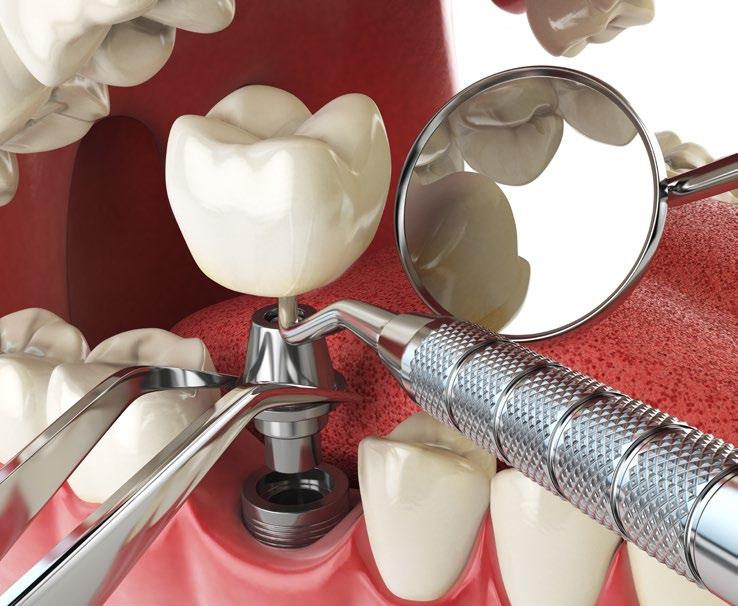

What are Dental Implants?

Dental implants are titanium posts surgically inserted into the jawbone, where they serve as a sturdy anchor for replacement teeth. Unlike dentures or bridges, which rest on top of the gums, implants integrate with the bone, a process known as osseointegration. This integration stabilizes the implant and makes it a permanent fixture in the mouth. The result is a replacement tooth that looks, feels, and functions like a natural tooth.

Creating a New Look with Dental Implants

One of the most significant advantages of dental implants is their ability to restore a natural-looking smile. They are customdesigned to match the natural color and shape of the patient’s existing teeth, blending seamlessly into the mouth. This can dramatically improve a person’s appearance, making them look younger and healthier. For many, this can lead to a renewed sense of self-esteem and vitality, particularly important as they age.

Implants act like natural tooth roots, promoting bone growth and preventing bone loss. Maintaining this bone structure not only supports facial features but also prevents the aging appearance that often accompanies tooth loss.